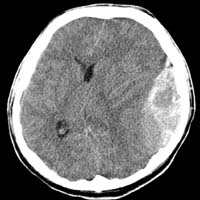

<µÎ°³°ñÀý>

<¼±»ó°ñÀý>

<ÇÔ¸ô°ñÀý>

µÎ°³°ñÀýÀÇ

³úCT ¼Ò°ß

<±Þ¼º°æ¸·¿ÜÃâÇ÷>

<¸¸¼º°æ¸·ÇÏÃâÇ÷>

ÁÂ)

ÁÂÃø ÃøµÎºÎ¿¡ ·»Áî¸ð¾çÀÇ °æ¸·¿Ü ÃâÇ÷ÀÇ

CT¼Ò°ß

¿ì) °æµµÀÇ ¿Ü»ó¿¡µµ

¹ß»ýÇÏ°Ô µÇ´Â ¸¸¼º°æ¸·ÇÏÃâÇ÷ÀÇ ³úMRI¼Ò°ß